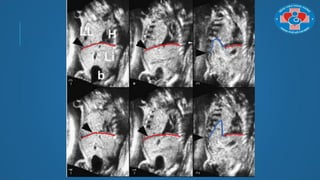

QUAN SÁT CẤU TRÚC KHÓ

Chẩn đoán các bệnh lý cần mặt cắt dọc giữa (thiểu sản/bất sản thể chai, thiểu sản

thùy nhộng)

QUAN SÁT CẤUTRÚC KHÓ Chẩn đoán các bệnh lý cần mặt cắt dọc giữa (thiểu sản/bất sản thể chai, thiểu sản thùy nhộng)